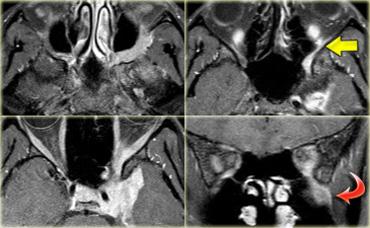

U thần kinh bao (Schwannoma) vùng góc cầu tiểu não với các đặc điểm điển hình của u ngoài trục (Chuỗi xung T2W)

Chuỗi xung T2W cho thấy một u thần kinh bao (schwannoma) nằm ở góc cầu tiểu não (CPA).

Trường hợp này minh họa rõ nét các dấu hiệu điển hình của u ngoài trục.

Có khe dịch não tủy (mũi tên vàng).

Các mạch máu dưới nhện chạy trên bề mặt não bị tổn thương đẩy lệch (mũi tên xanh lam).

Có chất xám nằm giữa tổn thương và chất trắng (mũi tên đỏ cong).

Khoang dưới nhện bị giãn rộng do sự phát triển của tổn thương ngoài trục có xu hướng đẩy lùi não.

Tất cả các dấu hiệu này cho thấy đây là một u ngoài trục điển hình.

Tại vùng góc cầu tiểu não, 90% các u ngoài trục là u thần kinh bao (schwannoma).